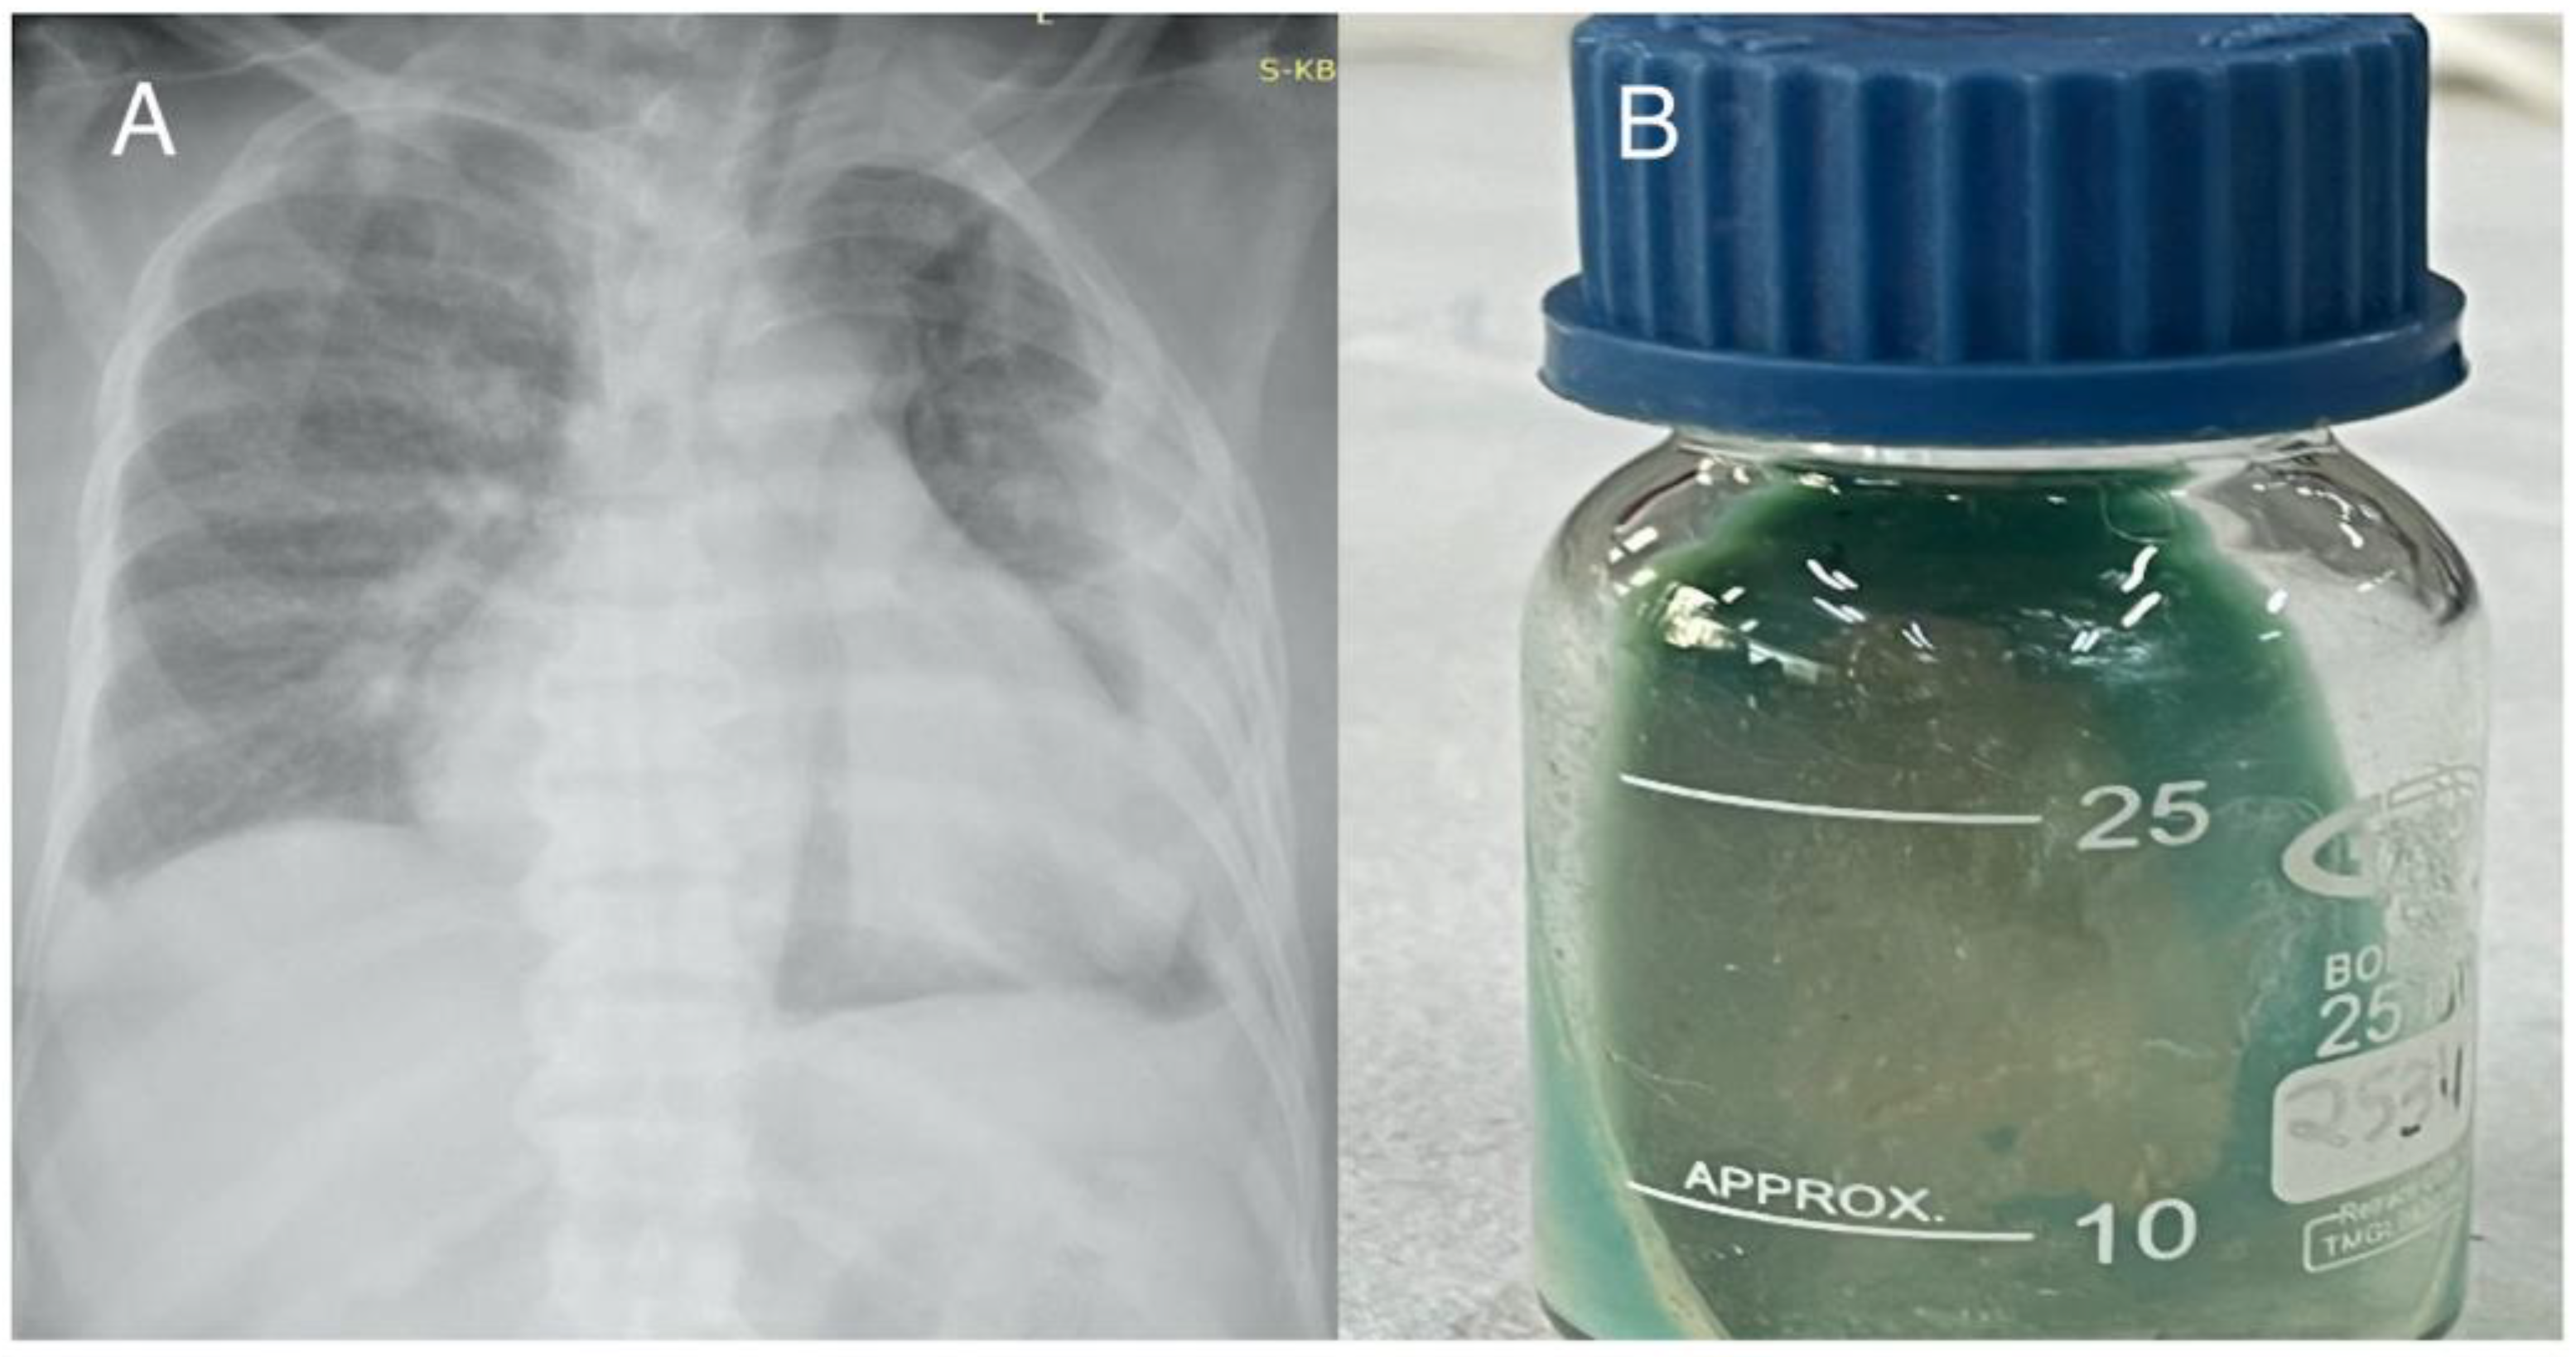

Case 1

Case 2

Case 3

Case 4